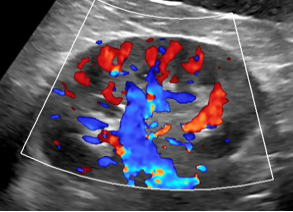

彩超:全称彩色多普勒超声,以B超为基础,在黑白图像上叠加彩色血流信号(红/蓝表示血流方向)。

彩超屏幕上怎么没有彩色图像?彩超中“彩色”两字的含义通俗地说其实是为了提示血管的血流方向,一般有红色和蓝色两种。医生通过血流方向判断检查中的脏器是否有血供以及血流方向以协助诊断疾病。所以说,彩超是彩色的,但是不等同于您家里的彩色电视机。